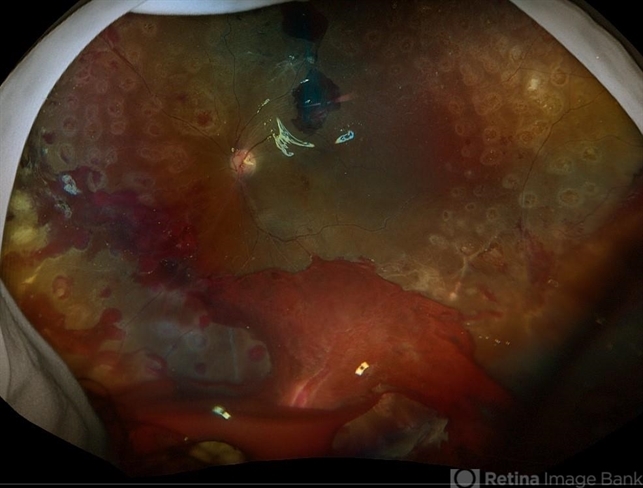

- retinal detachment of the macula, Diabetic Tractional Detachment, silicone oil

- 21 year old male 1 week s/p PPV/laser/STR/SO. Eye is stable, PRHs inferior and superior, possible traction from PRH/membrane. Will observe and let clot liquify, will consider scleral buckle if no improvement